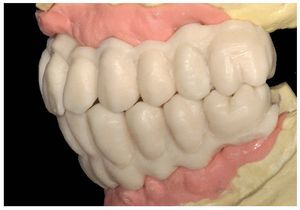

Pese a ello, es importante someter las estructuras a un control visual y mecánico, a fin de corregir eventuales discrepancias menores (figs. 99 a 102). A continuación se procede al montaje utilizando dientes protésicos prefabricados de composite (SR Phonares NHC, Ivoclar Vivadent, Ellwangen, Alemania), los cuales reproducen el tipo funcional correspondiente en virtud de sus propiedades morfológicas y estructurales y se integran armoniosamente en cuanto a su longitud dental (figs. 103 a 105). Durante la comprobación de las restauraciones protésicas, se evalúan clínica y radiológicamente ante todo la pasividad y la precisión del ajuste de la estructura. Acto seguido se lleva a cabo una comprobación de la oclusión y de la dimensión vertical, del estado de las prótesis y del tejido blando en la cresta alveolar, así como la verificación del espacio libre lingual, incluida la fonación, y el apoyo de los labios y las mejillas (figs. 106 y 107). También se debe comprobar la facilidad de higiene de la restauración de acuerdo con las habilidades manuales del paciente. A continuación se debe verificar la posición tridimensional de los dientes anteriores con los labios cerrados y durante la sonrisa, así como el aspecto global de la rehabilitación protésica.

Figs. 103 a 105. Recubrimiento estético de las estructuras con dientes protésicos prefabricados de composite. Vista frontal y lateral a derecha e izquierda.

Durante la fase de laboratorio final pueden ser necesarios diversos ajustes estéticos y funcionales. A continuación puede confeccionarse la restauración definitiva (figs. 108 a 111). Posteriormente se procede al control final mediante sendos montajes cruzados de la restauración definitiva y del modelo de planificación (figs. 112 a 115).

Figs. 108 a 111. Vista frontal y lateral de los puentes implantosoportados terminados.